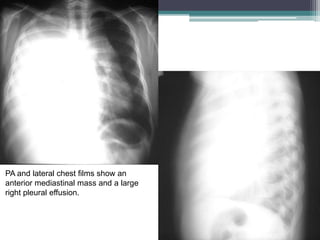

PA and lateral chest films show an

anterior mediastinal mass and a large

right pleural effusion.

Two contiguous slices

from an enhanced chest

CT exam show a

homogenous, solid,

anterior mediastinal mass

and a large right pleural

effusion.

Dx-Lymphoma, Non-

Hodgkin, Anterior

Mediastinal